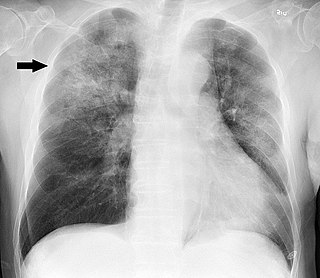

Diagnóstico inadecuado de neumonía entre adultos hospitalizados

En este estudio de cohorte, el diagnóstico inadecuado de neumonía adquirida en la comunidad (NAC) entre los adultos hospitalizados fue común, particularmente entre los adultos mayores, aquellos con demencia y aquellos que presentaban un estado mental alterado. El tratamiento completo con antibióticos en personas diagnosticadas inadecuadamente con NAC puede ser perjudicial. JAMA Intern Med. 25 de marzo de 2024